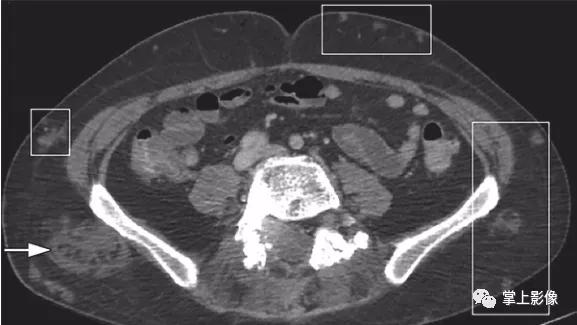

60岁女性转移性卵巢浆液性腺癌。轴位CT显示卵巢浆液性癌淋巴结转移(正方形轮廓)。注意钙化(箭头),它类似于此患者其他部位的转移性疾病(未显示)